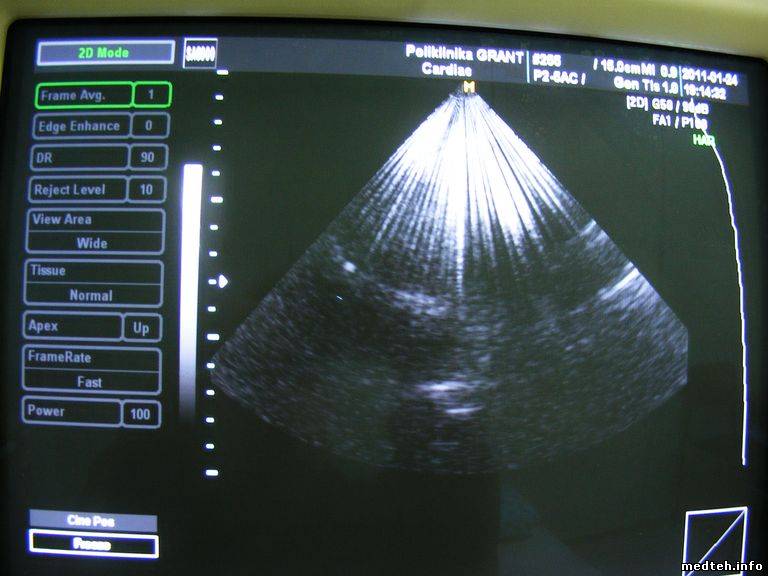

Помехи выглядят как показано на фото, фото сделано при работе с разными датчиками, одно фото когда стоит кардиологический датчик, другое фото, когда стоит гинекологичекий датчик.

3090305.jpg (164.8 Kb) · 1352311.jpg (68.7 Kb)

На фото где помеха более интенсивная сверху, работет кардиологический датчик, на фото где помеха слева идет к низу по всему полю сканирования работает гинекологичекий датчик.